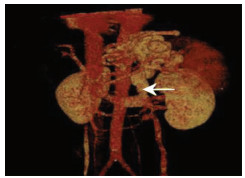

Value of coronary-caval shunt combined with splenectomy in portal hypertension

Weijie WANG, Rongtao ZHU, Ruopeng LIANG, Jian LI, Chixian ZHANG, Dexu LI

2021, 37(4): 898-901. DOI: 10.3969/j.issn.1001-5256.2021.04.034

Abstract(813) HTML (217) PDF (4530KB)(40)